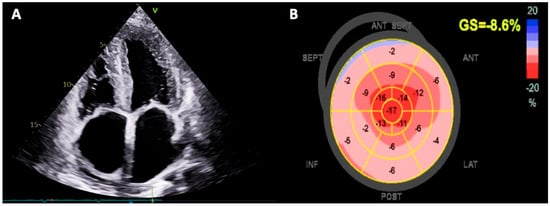

6.2.2. Echocardiography

- Phelan, D.; Collier, P.; Thavendiranathan, P.; Popović, Z.B.; Hanna, M.; Plana, J.C.; Marwick, T.H.; Thomas, J.D. Relative Apical Sparing of Longitudinal Strain Using Two-Dimensional Speckle-Tracking Echocardiography is Both Sensitive and Specific for the Diagnosis of Cardiac Amyloidosis. Heart 2012, 98, 1442–1448. [Google Scholar] [CrossRef]